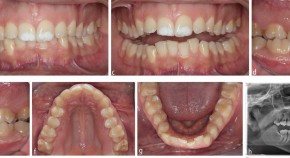

Bringing together a selection of articles from across the BDJ Portfolio, this Collection relates to the theory and practice of orthodontics. It features the BDJ Special Issue on the Orthodontic-Restorative Interface with contributions by leading national and international clinicians and researchers. Guest edited by Padhraig Fleming, it provides a contemporary, international perspective on adult orthodontics and combined orthodontic-restorative care.